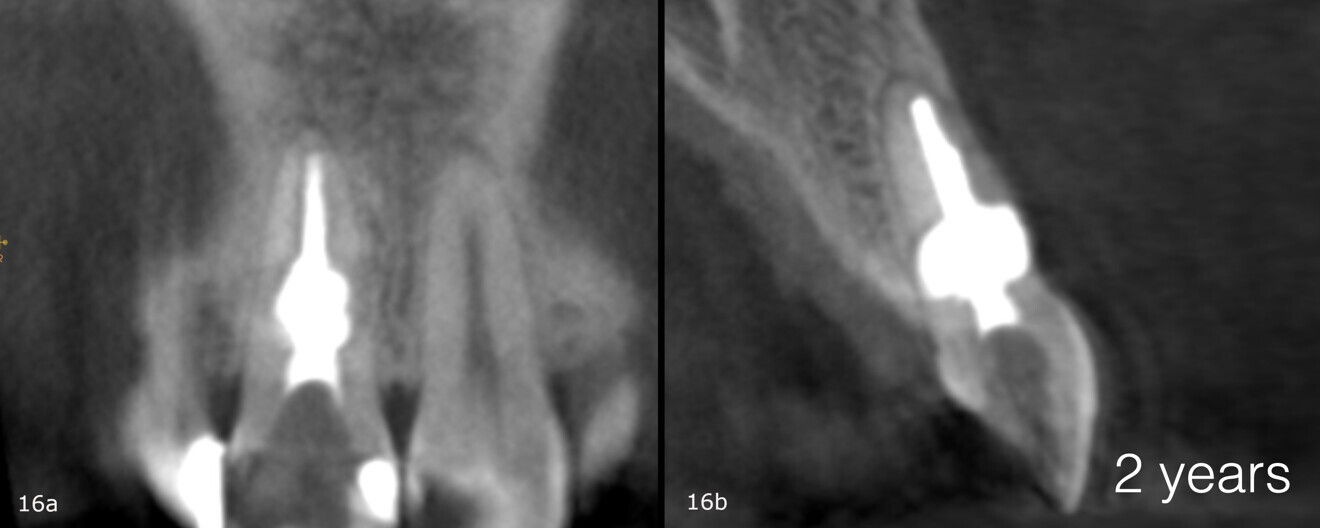

Recall appointments was performed after two (Figs. 16a & b) and four years (Figs. 17a & b). The radiographic examination showed the presence of bundle bone. The periodontal status was stable, and the tooth remained asymptomatic.

Figs. 16a & b: CBCT scan taken two years after the treatment.